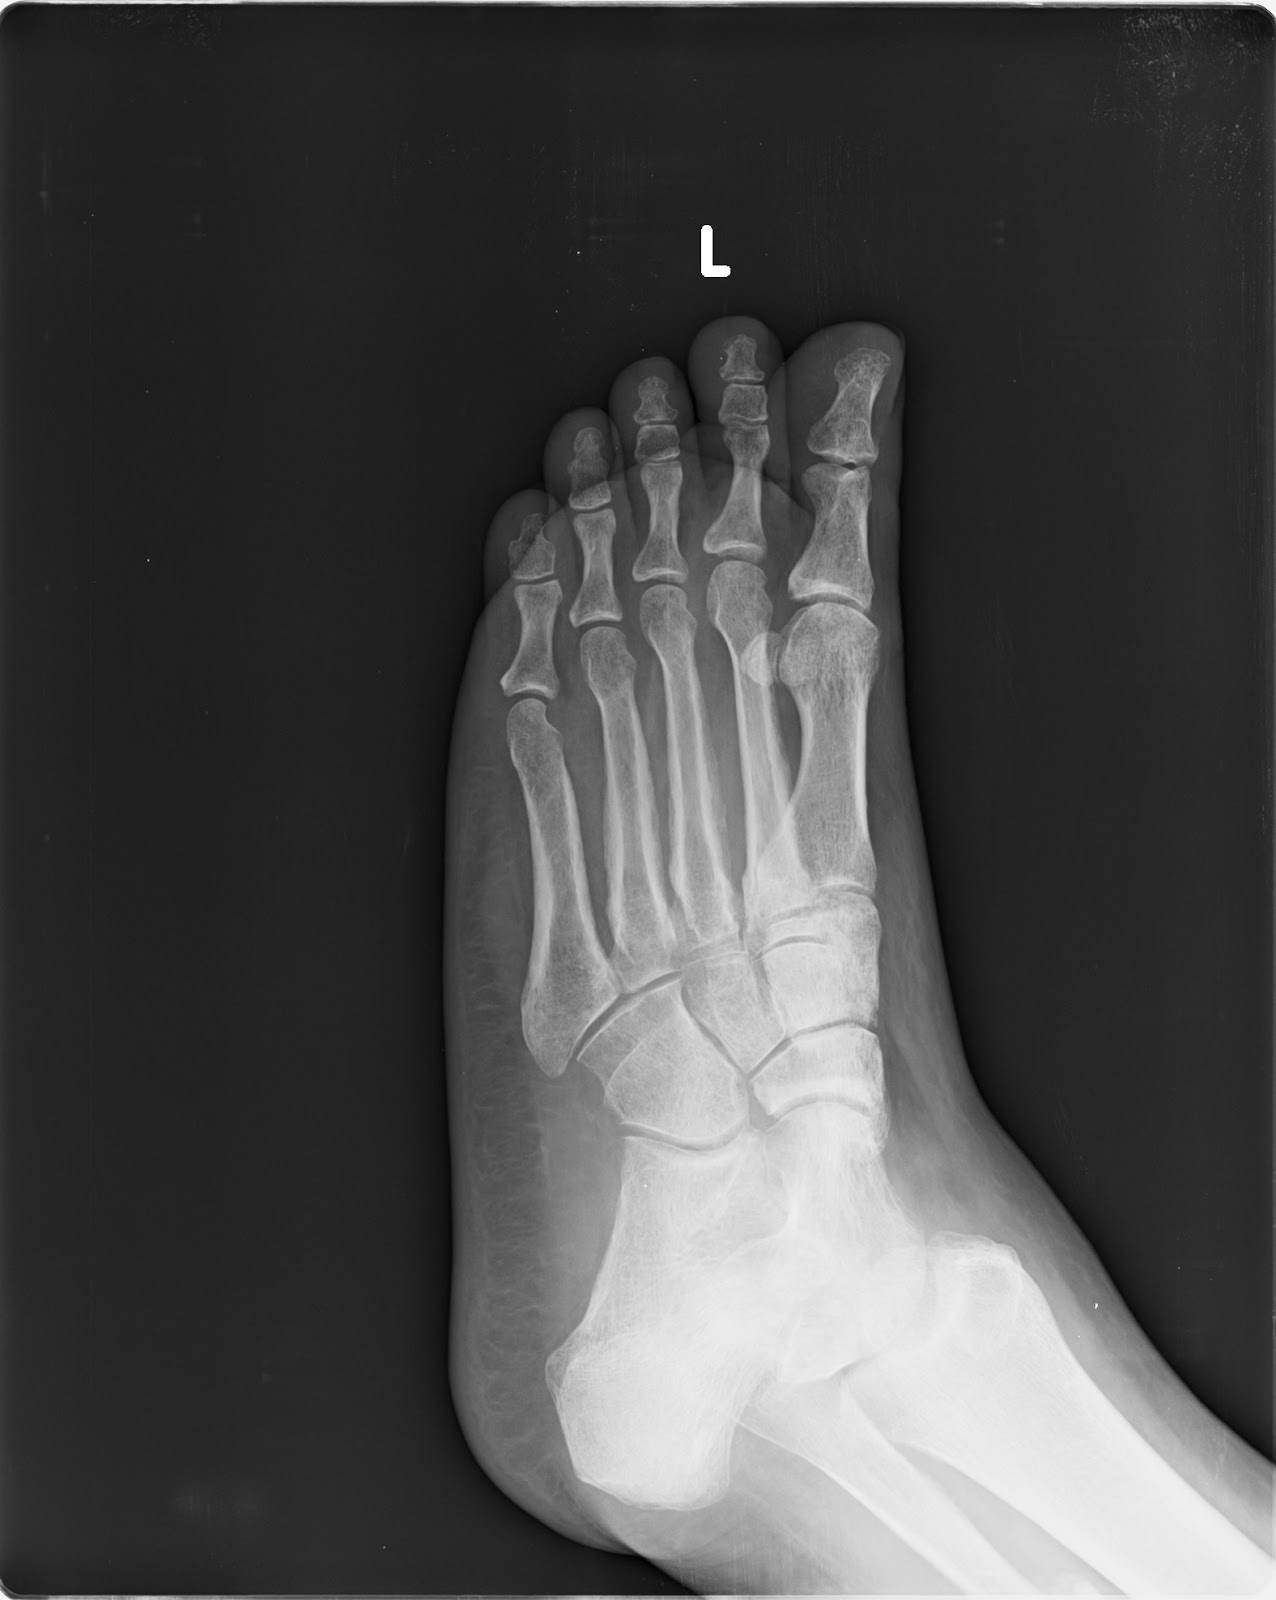

Xrays dated 5 June 2014 taken right after the fracture showing no ankle injury but only a fibula fracture and the opinion of three doctors including a radiologist and 2 orthopedics (Dr Shailza Aggarwal, and Dr Fahad and Dr Sandeep Chauhan) that there was no ankle injury and that the fibula fracture did not require surgery and would heal in a cast.

Xrays taken on 5 June 2014 the date of the fibula fracture